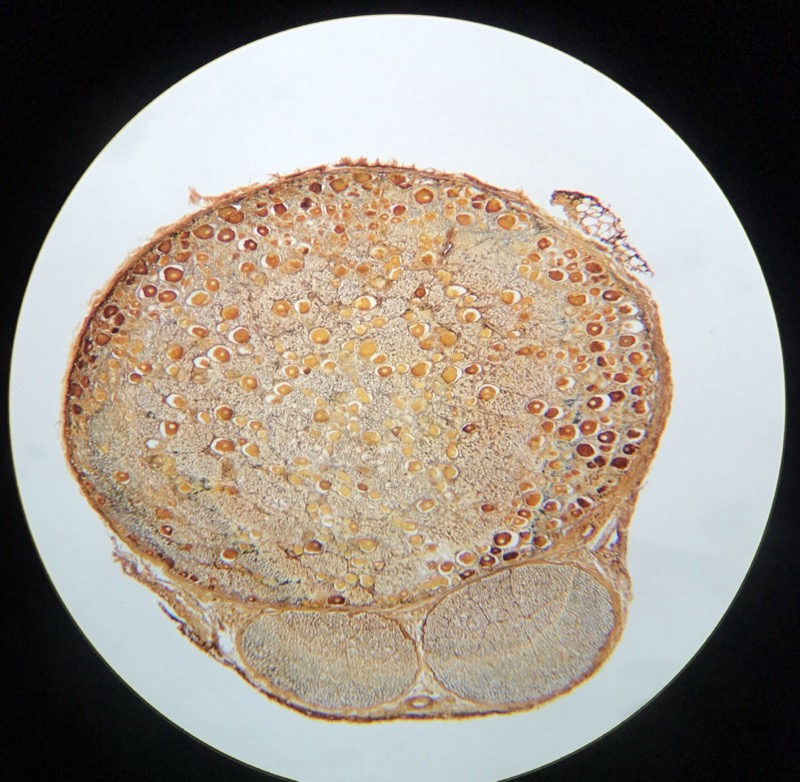

| 1:3:6 | Brosk elastiskt och hyalint | ![]() ![]() ![]() ![]() ![]() ![]() ![]() |

| 1:6:3 | Spinalt Ganglion | ![]() ![]() ![]() |

| 1:6:4 | Sympatiskt Ganglion | ![]() ![]() |